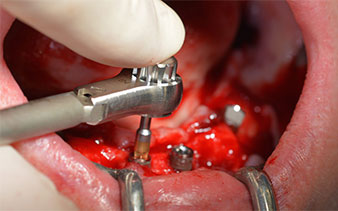

Zunächst wurde das Foramen mentale als limitierende anatomische Struktur dargestellt und die krestale Kortikalis mit dem geraden Handstück und einem großen Rosenbohrer geglättet (Abb. 4).

Das chirurgische Protokoll der verwendeten Implantate (SKY, bredent medical) schreibt eine Umdrehungszahl von 1.200/min für die Pilotbohrungen vor (Abb. 7–9).

Dies entspricht der nächsten Position der Voreinstellung am Implantmed. Zu erkennen ist die etwa 45-Grad-Schräghaltung des W&H Winkelstückes nach mesiokaudal in Regio 45, um den Nervus mentalis zu schonen. Das Foramen mentale gilt als anatomische Orientierung für alle Bohrungen in diesem Bereich. Die anschließenden Bohrungen werden mit einer reduzierten Umdrehungszahl von 300/min durchgeführt (Abb. 10 und 11).

Die nächste programmierte Einstellung ist bereits die Implantateinbringung. Die Implantate werden in unserem Hause standardmäßig mit einer Kraft von 32Ncm inseriert (Abb. 12 und 13).

Die absolute Voraussetzung für die Sofortversorgung ist die hohe Primärstabilität. Um diese zu erfüllen, wurde in diesem Fall auf ein Gewindeschneiden verzichtet. Die hier verwendete Antriebseinheit Implantmed von W&H besitzt hierfür einen eigenen Modus, der ebenfalls direkt anwählbar und für viele Indikationen unverzichtbar ist. Die letzten Umdrehungen bei der Implantateinbringung überschritten den Wert von 32Ncm und wurden manuell durchgeführt. Hierfür empfiehlt es sich, die Selbstschneidefunktion der Implantate auszunutzen und das Implantat mehrmals vorwärts und rückwärts zu drehen. So gelangt das Implantat schrittweise näher bis zur endgültigen Position, ohne zu starken Druck auf den Knochen auszuüben (Abb. 14).

Um die Divergenz der distalen Implantate auszugleichen, werden abgewinkelte Abutments (35 Grad) eingeschraubt, sodass die Austrittsprofile sämtlicher Implantate möglichst senkrecht zur Kauebene stehen. Dies ist Voraussetzung, um die provisorische und später auch die endgültige Versorgung okklusal verschrauben zu können (Abb. 15 und 16).